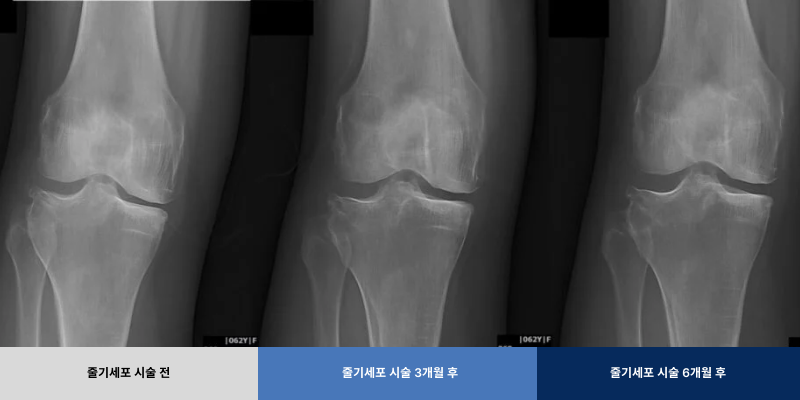

무릎 관절염 치료 시술 전후

무릎관절염 골수 줄기세포 시술 전후 63세 여성